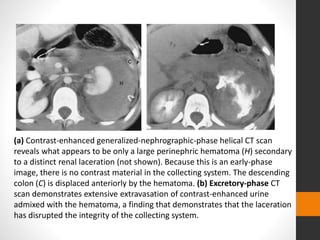

(a) Contrast-enhanced generalized-nephrographic-phase helical CT scan

reveals what appears to be only a large perinephric hematoma (H) secondary

to a distinct renal laceration (not shown). Because this is an early-phase

image, there is no contrast material in the collecting system. The descending

colon (C) is displaced anteriorly by the hematoma. (b) Excretory-phase CT

scan demonstrates extensive extravasation of contrast-enhanced urine

admixed with the hematoma, a finding that demonstrates that the laceration

has disrupted the integrity of the collecting system.